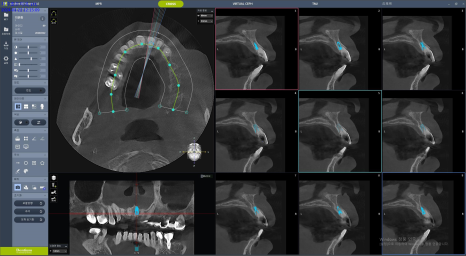

3차원 분석을 위한 Dentium CT 촬영을 통해 수술 계획을 원장이 직접 수립합니다. 공장형 치과에서는 오늘 누가 어디에 몇 개 임플란트를 심는지 수술방에 가서야 확인하는 경우도 있습니다. 우리는 언제나 원장이 직접 진단하고 상담, 수술 및 보철 수복 계획까지 직접 세우기 때문에 환자 개개인에 맞게 충분한 고민 후에 수술에 임할 수 있습니다.

디지털 내비게이션은 치과의사의 편의를 위해 개발된 수술 가이드(guide)입니다. 디지털 내비게이션을 잘 다루기 위해서는 가이드 없이 진행하는 임플란트 식립 - 즉 프리핸드(free-hand) 수술 실력이 뒷받침 되어야 합니다. 우리 치과는 원장이 직접 프리핸드 수술 경험을 토대로 디지털 가이드 계획을 수립하는데, 이것은 모든 수술 과정을 의사가 직접 통제하고 책임지기 위함입니다. 원가이드, 디오나비 등 임플란트 회사 직원들에게 외주 맡겨 디자인한 가이드를 그대로 받아 사용하는 일은 없습니다.